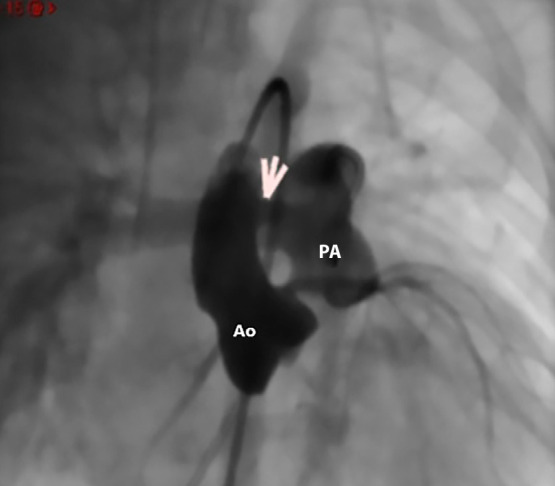

主动脉肺窗是一种罕见的先天性心脏缺陷。无其他相关异常的孤立性主动脉肺窗占所有病例的25%。手术封闭一直是,并且仍然是许多心血管中心的黄金标准。然而,经皮闭合已经成为一种可行的选择,使用各种类型的闭塞装置,根据缺损的形态、大小和边缘来选择,以尽量减少并发症,如瓣膜干扰或冠状动脉口梗阻。我们报告一例婴儿与孤立的主动脉肺窗成功治疗经皮封闭使用肌肉室间隔缺损闭塞装置,没有并发症。术后48小时患者出院。

The aortopulmonary window is a rare congenital heart defect. Isolated aortopulmonary window, without other associated anomalies, accounts for up to 25% of all cases. Surgical closure has long been, and remains, the gold standard in many cardiovascular centres. However, percutaneous closure has emerged as a viable alternative using various types of occluder devices, selected based on the morphology, size, and rims of the defect to minimise complications such as valvular interference or coronary ostial obstruction. We report the case of an infant with an isolated aortopulmonary window successfully treated with percutaneous closure using a muscular ventricular septal defect occluder device, with no complications. The patient was discharged 48 hours after the procedure.